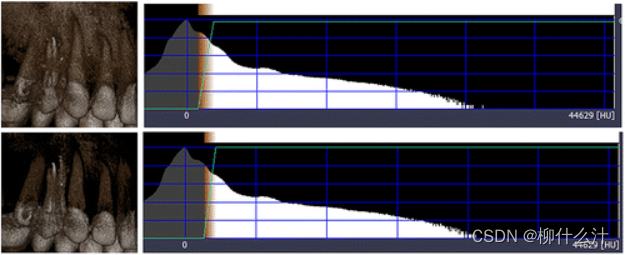

最基本的处理方法是窗口/水平转换。这种转换是为了优化图像的对比度,只显示全部灰度值范围的一部分。这个量是由窗宽(W)决定的。例如,W为1000意味着考虑显示1000个灰度值,最低的灰度值(以及低于它的所有值)被显示为黑色,最高的(以及高于它的所有值)被显示为白色。窗口级别(L)决定了窗口宽度内的中心灰度值。例如,W/L为1000/0意味着-500和+500之间的灰度值被考虑显示,所有其他值显示为黑色(<-500)或白色(>+500)。这样,显示显示器和人眼的全部对比度就被应用于这个特定的灰度值范围。W/L操作可用于不同的目的;在牙科CBCT中,它主要用于优化骨密度范围内的对比度,即通过使用与骨灰度值相对应的L值

窗口/水平的影响。左图:大宽度的窗口覆盖整个图像的灰度值范围,导致图像对比度差。中间:中等宽度的窗口覆盖软组织和骨骼的灰度值,导致良好的整体对比度。右图:小宽度的窗口有一个高级值,导致骨和牙齿的高对比度。